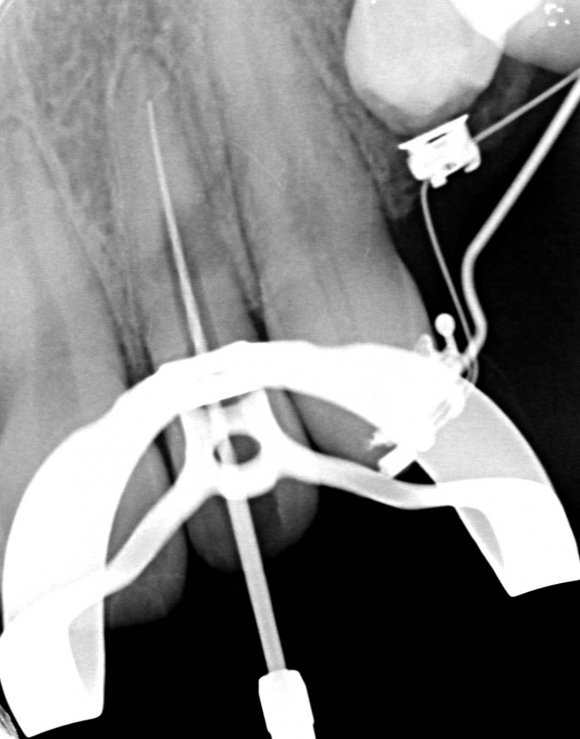

Also, there were signs in favor of internal resorption. The defect was below the cervical part, which is not typical of external cervical resorption. The response to cold stimuli reduced, which is not characteristic of external resorption, as it affects the pulp only in the last stages of tooth structures decay. Furthermore, the X-ray obliteration of the root canal beyond the resorption area is not characteristic of external resorption. Visit 1: Pre-op X-ray plus anesthesia with sol. Ubisthesini 4% -1 ml, isolation with rubberdam. The access was made as close as possible to the incisal edge. When opened, at first glance the pulp chamber looked quite II.